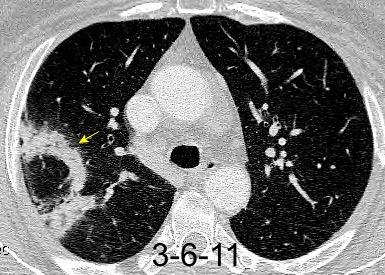

NEUMONITIS POR RADIACIÓN

Neumonitis evidente de 4-12 semanas después de terminar RXT. Fibrosis evidente en 3-4 meses. Estable de 912 meses.

Ca. de mama izquierda. 3/7/09 Radioterapia

La lesión típicamente limitada al campo de irradiación.

Müller NL. 2010

Induce neumonitis. “Tangential beam” para pared torácica.

Jung JI et al. Thoracic Manifestations of Breast Cancer and Its Therapy. Radiographics 2004